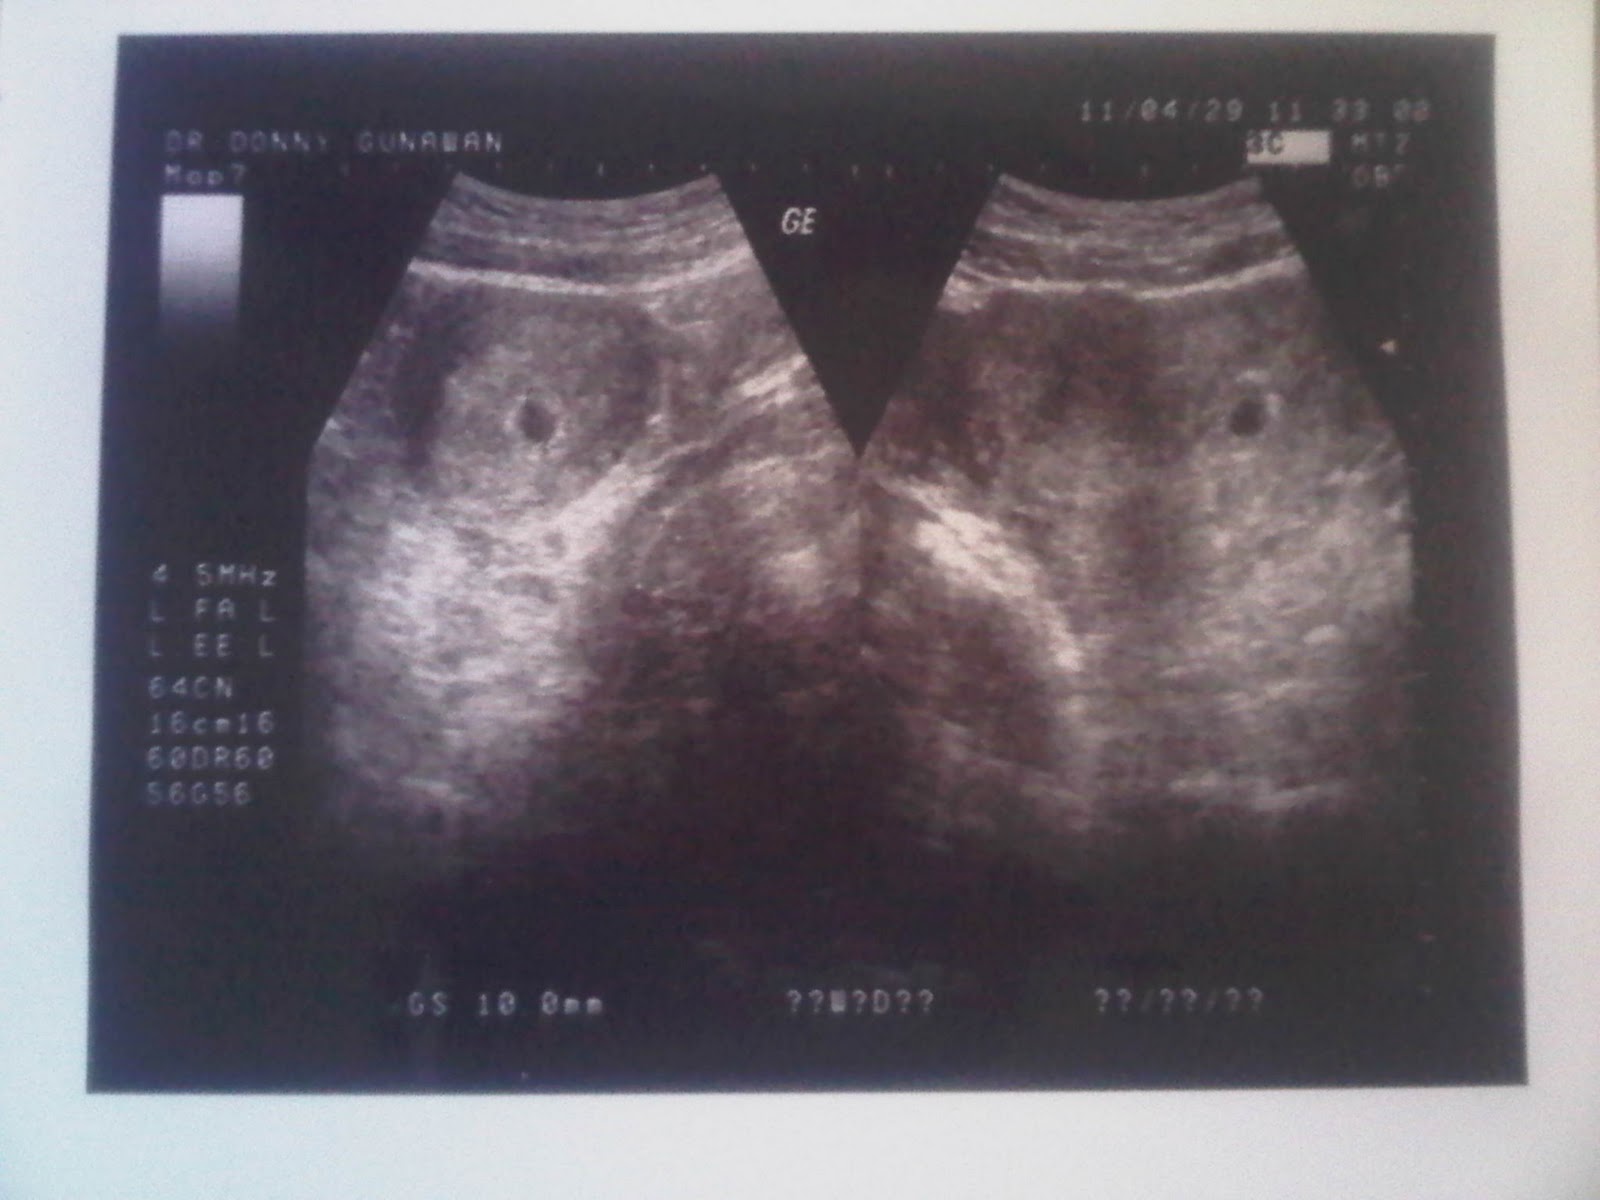

Hasil periksa n usg 8bln. - IbuHamil.com

Hasil periksa n usg 8bln. - IbuHamil.com from ibuhamil.com